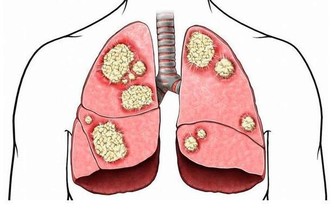

腎臟也一樣,在長期工作壓力和毒素的接觸下,腎臟,尤其是尿液流經的腎小管上皮細胞會發生一些量變,從量變轉變到質變。這時候就產生了腎臟最初的病變。在發生最初病變的時候,隨著病變不斷地長大,這種生長逐漸失去調控,就形成了腫塊,也就是說腎臟上長了一些我們所說的惡性腫瘤。

腎臟的惡性腫瘤分為很多種,最常見的就是腎細胞癌。